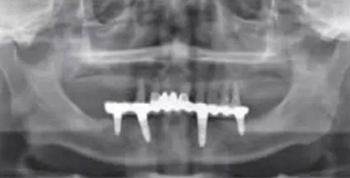

影像學(xué)檢查:下頜修復(fù)體與種植體邊緣密合,種植體周圍并無明顯異常,14、13、21、22、24、25見根尖陰影,牙槽骨吸收至根尖1/3。23見牙周膜增寬影,牙槽骨吸收至根中1/2(圖2,3)。診斷:上頜牙列缺損(15、16、17、26、27缺失);上頜廣泛性重度牙周炎;14、13、21、22、25根尖周炎。

圖3 術(shù)前曲面斷層全景片檢查

術(shù)后曲面斷層全景片(圖19)可見種植體在上頜位置較為理想,同時(shí)可見臨時(shí)義齒種植體開孔位置在13、23舌側(cè)、16、26牙合面近中,上下頜咬合關(guān)系理想。患者對種植臨時(shí)修復(fù)義齒滿意。